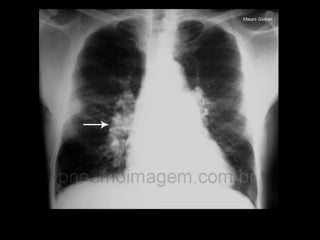

Exames de imagem: Rx Tórax

Primeiro passo na investigação radiológica da

suspeita de HAP;

Achados típicos: aumento do calibre das artérias

centrais, com rápido afilamento dos vasos à medida

que progridem para a periferia;

A área cardíaca pode estar aumentada ou normal;

Calcificação vascular: associado a alta RVP;

Sensibilidade baixa;

Útil para afastar ou sugerir causas de HAP;

Radiografia de tórax normal